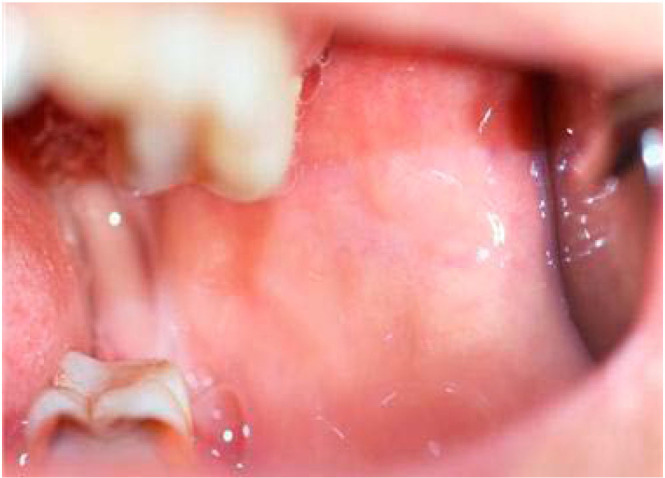

Basal cell adenocarcinoma, considered to be the malignant counterpart of basal cell adenoma, is a rare, low-grade malignant tumor of the salivary glands, accounting for 1-2% of salivary gland malignancies. It predominantly affects the parotid gland, while involvement of the minor salivary glands is exceptionally rare. This report presented a case of basal cell adenocarcinoma involving the left retromolar trigone in a 54-year-old woman. The initial provisional diagnosis suggested a benign or low-grade malignant salivary tumor. Advanced magnetic resonance imaging techniques, including diffusion-weighted imaging and apparent diffusion coefficient analysis, aided in the preoperative prediction of malignancy, and an incisional biopsy confirmed the diagnosis of basal cell adenocarcinoma. This case underscored the challenge of distinguishing basal cell adenocarcinoma from benign salivary tumors, as clinical and imaging features often overlap. Surgical excision remains the primary treatment, yielding favorable outcomes; however, long-term follow-up is crucial due to the risk of recurrence.

Abstract Image